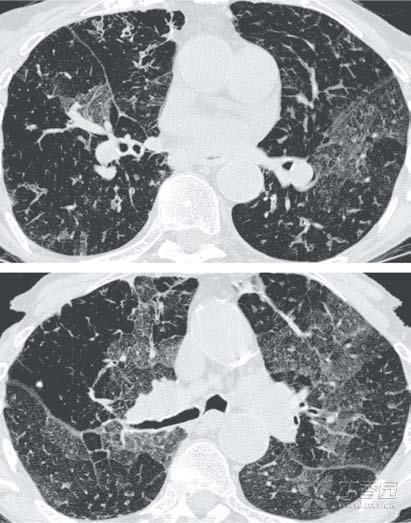

闭塞性支气管炎是一种罕见、致命且不可逆的阻塞性肺病,

若患上了这种疾病,别说抽烟了,可能很长一段时间都要在抽血中度过了。